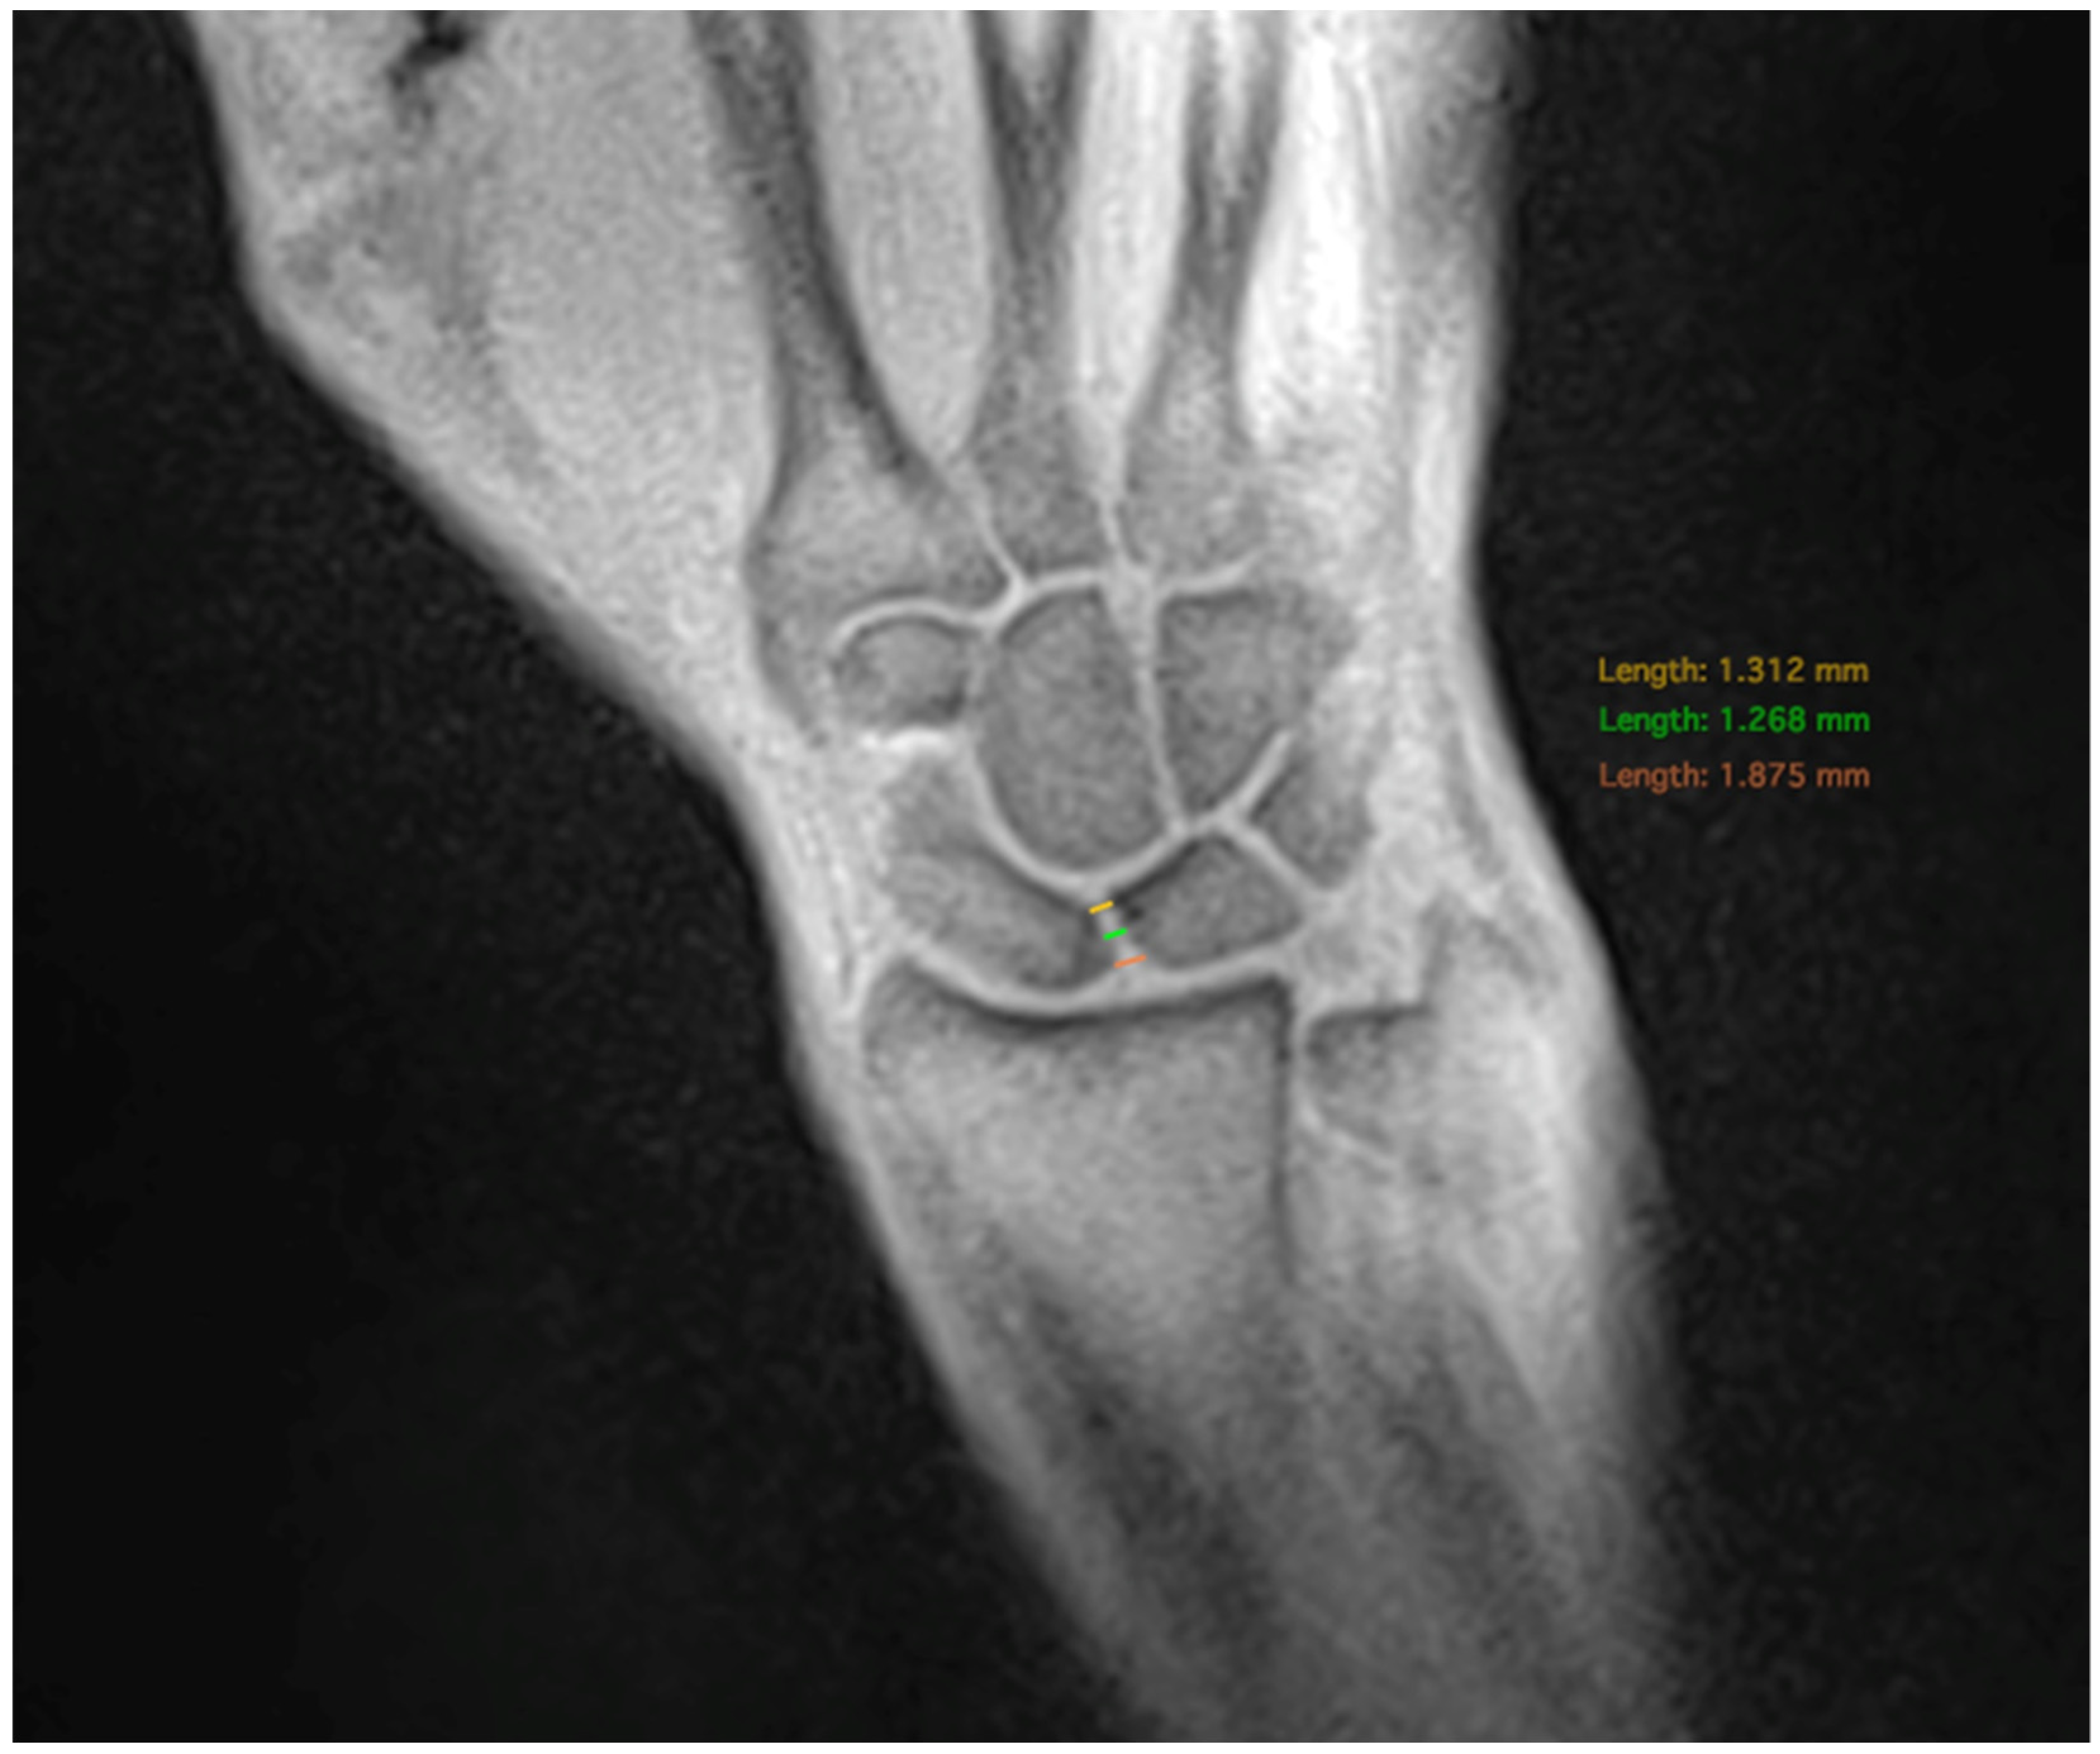

The SL distance was measured at three different positions with the distal, medial, and proximal bone points of the scaphoid and lunate serving as the anatomical landmarks. (Figure 2). Measurements were performed on both static and dynamic images.

Figure 2. Measurement of the SLJW in three positions: at the proximal landmark (red), the medial landmark (green) and the distal landmark (yellow).